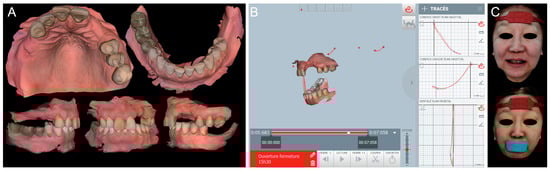

Digital impressions of the patient’s existing maxillary and mandibular arches and the MMR were obtained using the intraoral scanner (TRIOS 4; 3Shape A/S) (Figure 2A). The digital complete-arch casts were imported and aligned into the jaw motion system (MODJAW; MODJAW). The mandibular movements were registered following the manufacturer’s protocol (Figure 2B). Finally, the patient’s face was digitized with the facial scanner (Bellus3D Face Camera Pro; Bellus3D) and the AFT (AFT dental system) protocol (face and teeth aligners) (Figure 2C) [19].

Figure 2. Digital view of the initial situation: (A) 3D images (TRIOS 4; 3Shape A/S) of maxillary, mandibular, and MMR captured by IOSs; (B) functional mandibular movements recording with the jaw motion tracer (MODJAW; MODJAW); and (C) facial scans (Bellus3D Face Camera Pro; Bellus3D) with AFT aligners.

A 4D virtual patient was created by importing the scan data and mandibular motion files into the CAD software program Version 2.3 (Exocad DentalCAD; exocad GmbH). Data were aligned for the rehabilitation of the maxillary and mandibular arches (Figure 3A). A diagnostic waxing of the residual teeth and artificial teeth on the edentulous ridges was designed according to esthetic and functional parameters (Figure 3B). The static and dynamic occlusions were then adjusted and validated with the digital articulator and the mandibular motion.

Figure 3. (A) Creation of a 4D virtual patient by aligning digital data on CAD software (Exocad DentalCAD; exocad GmbH) and (B) occlusal and frontal views of digital waxing.